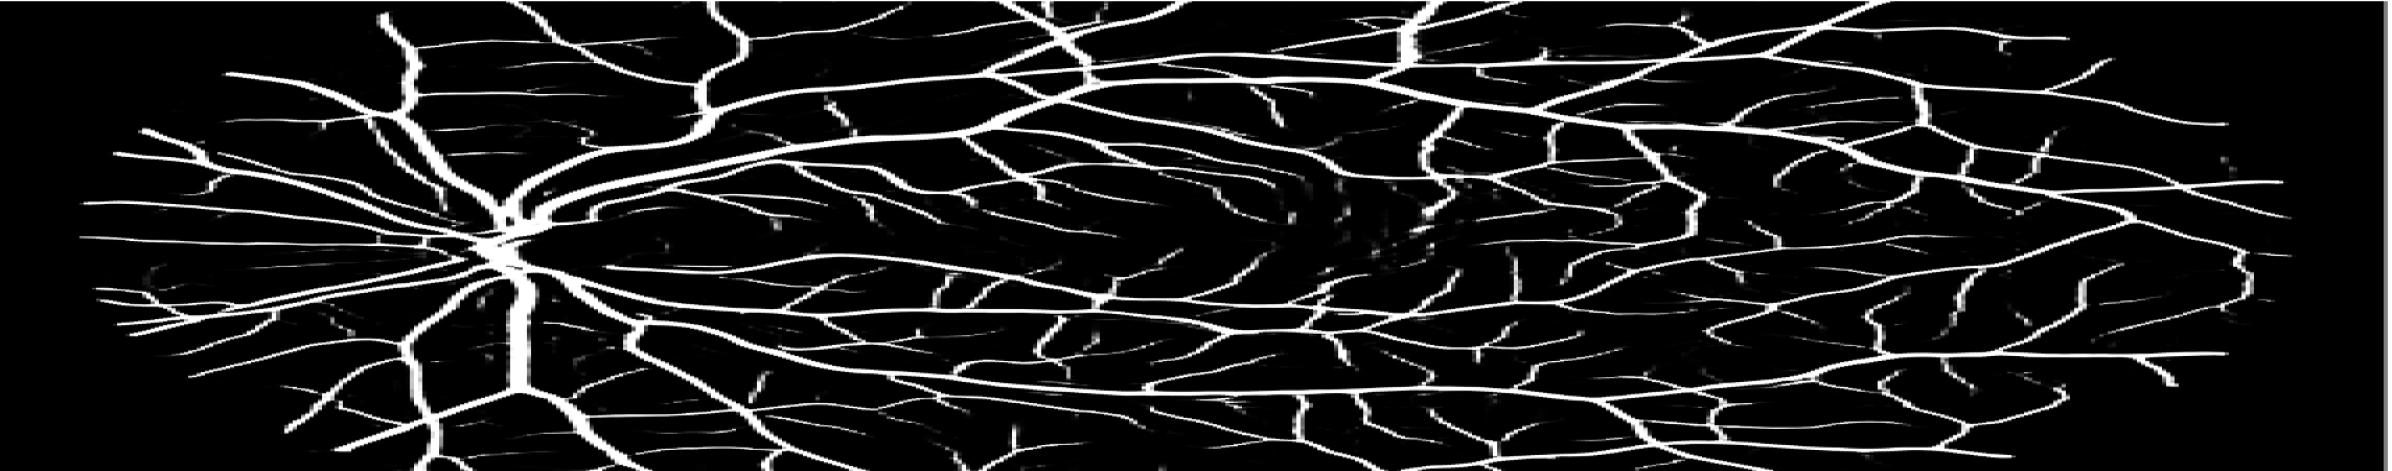

Figure 3: Qualitative results on all three segmentation tasks. The figure shows an example image, ground truth (GT) and predicted (PRED) segmentation mask for the skin lesion segmentation task (row 1), the polyp segmentation task (row 2) and retinal vessel segmentation task (row 3).

We have provided the additional qualitative results of our method for all three segmentation tasks. Fig. 5, shows the qualitative results of skin lesion segmentation, while Fig. 6 and Fig. 7, illustrate the visualization of retinal vessel and polyp segmentation tasks respectively.

Refer to caption

IMAGE

GROUND TRUTH

PREDICTED MASK

Figure 6: Visualizations of retinal vessel segmentation